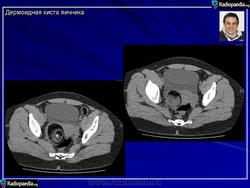

Зрелая тератома яичника.

Приложения:

101.pozhilye_kistoznoy_teratomy_yaichnika.jpg102.pozhilye_kistoznoy_teratomy_yaichnika.jpg103.pozhilye_kistoznoy_teratomy_yaichnika.jpg104.pozhilye_kistoznoy_teratomy_yaichnika.jpg